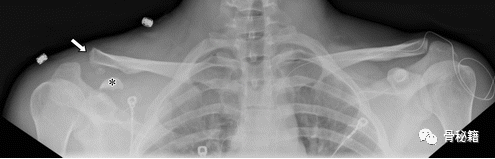

在急性创伤中,包括对侧在内的直立全景 Zanca 射线照相视图被广泛使用。双侧视图为正常关节配置和 AC 和 CC 距离提供参考,提高诊断准确性。通过测量和比较两侧而不是依靠目视检查进一步提高了准确性,CC 距离是最可靠的。通过悬吊或让患者保持 10-15 磅重物获得压力视图;这两种方法产生相似的结果。